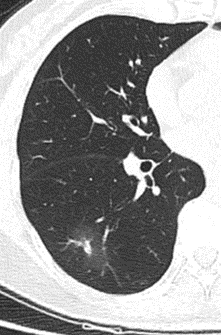

右下肺磨玻璃结节

2月后复查变淡消散